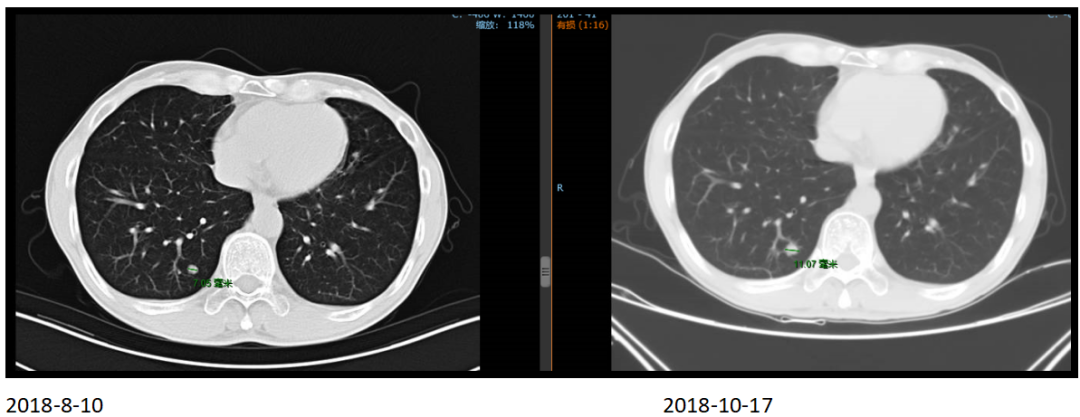

2018年8月10日复查胸部CT发现双肺多发小结节,遂定期观察随访。

2018年10月复查双肺结节较前增大。

2018年10月23日至2019年2月3日行顺铂+氟尿嘧啶联合赫赛汀方案治疗5周期,疗效评估PR。

2019年1月24日,经4个周期赫赛汀+DF后,患者肝脏转移灶明显缩小。

2018年10月17日,化疗前

2019年1月24日,化疗后